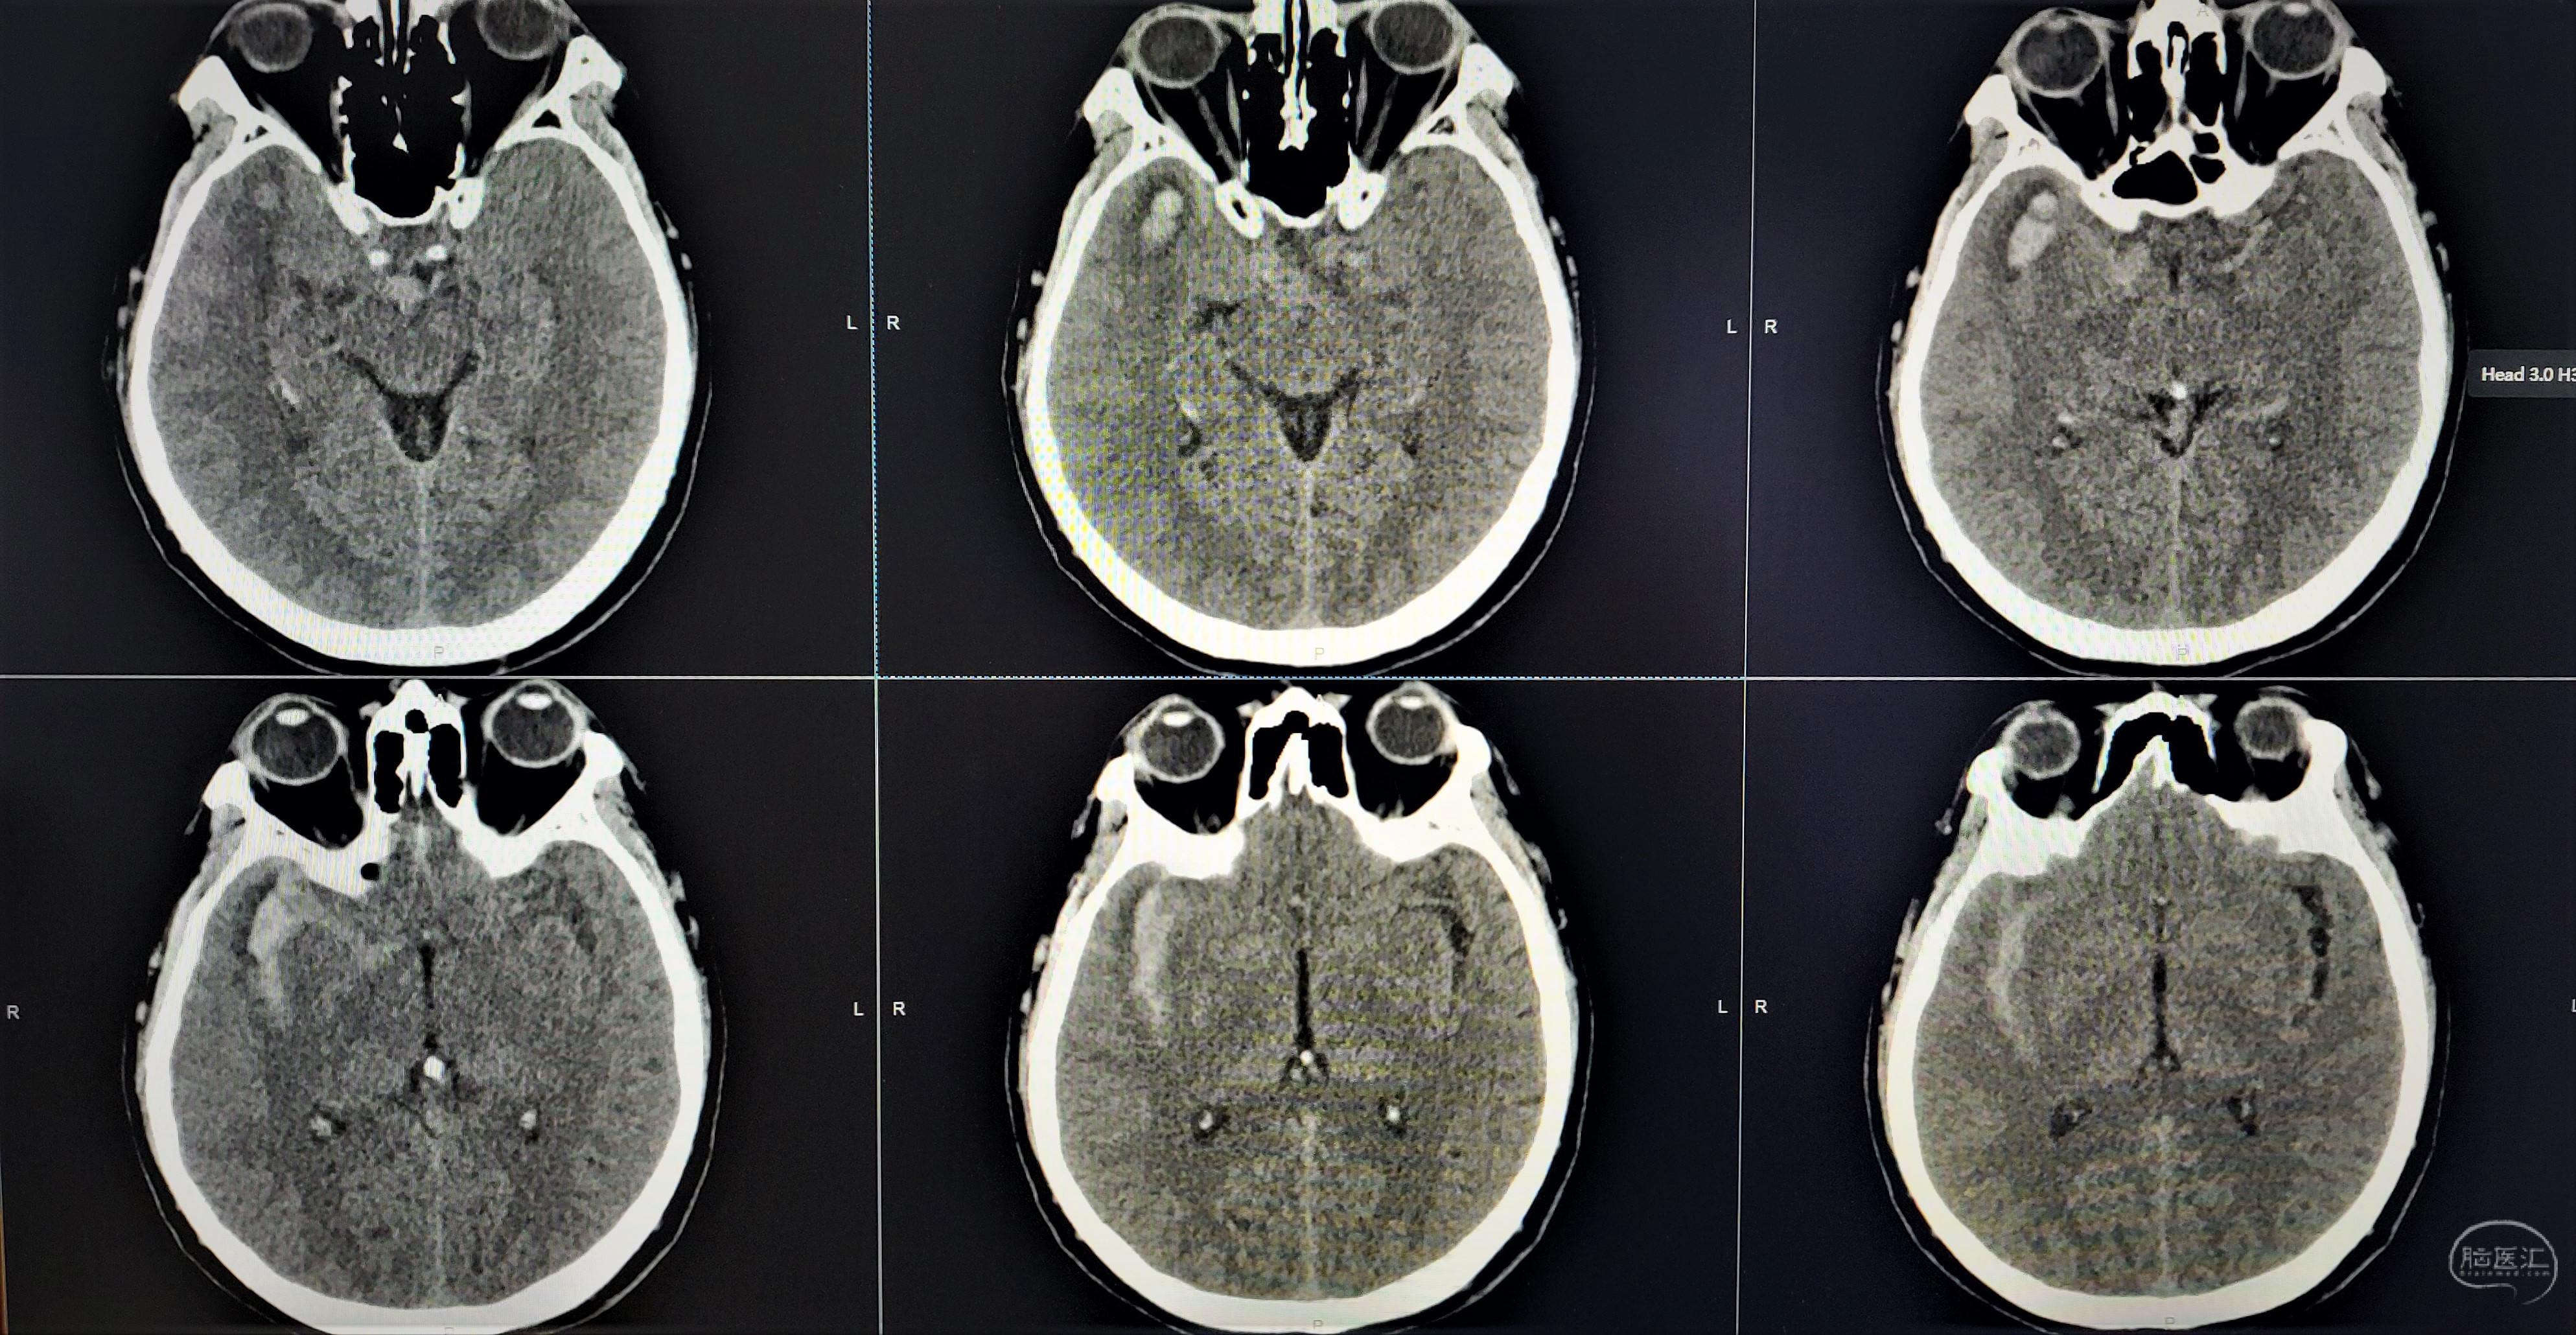

术前CT显示右侧外侧裂蛛网膜下腔出血。

术后第一天CT,血肿大部分清除,无明显脑梗死。

术后1月复查头颅CT及CTA